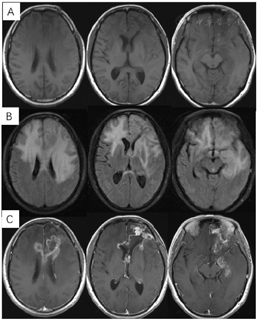

2018年3月、6月MR复查发现病灶范围逐渐增大(图6),提示不除外复发可能。患者除了轻微头痛之外并无明显不适,临床考虑假性进展,予安维汀100mg治疗后症状好转。2018年8月复查11C-MET PET/MR显像未见明显代谢增高病灶,证实为假性进展(图7)。2018年11月复查未见明显肿瘤复发,2019年3月2日MRI复查(图8)再次提示病变增大,考虑肿瘤进展。2019年3月行PD-1单抗(拓益)治疗,治疗过程中患者出现行走不稳,1月后患者不慎跌倒,外院就诊行颅脑CT未见明显出血。期间发现患者肝功能异常,给予护肝治疗后好转。2019年5月复查PET/MR(图9)提示左侧额叶前下部、左侧海马区及左侧颞叶前部蛋氨酸代谢较前次增高,其中左侧海马及左额叶直回ASL灌注相对增高,考虑复发可能,免疫治疗后存活。遂停用免疫治疗,根据患者全基因组测序结果选择靶向药物安罗替尼治疗(主要针对VEGFR、PDGFR、FGFR、c-KIT多个靶点),2019年12月复查PET/MR(图10)提示病变活性受抑。电话随访得知患者因武汉疫情影响无法按期治疗和复查,后合并肺部感染,于2020年8月去世。